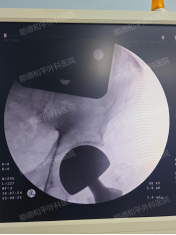

手术当日,副主任俞泉带领团队凭借丰富的临床经验和精湛的微创技术,有条不紊地开展人工股骨头置换手术。术中严格遵循精准操作原则,避开重要血管神经,优化手术流程,整个手术仅用1小时便顺利完成,出血量少,患者生命体征始终保持平稳。